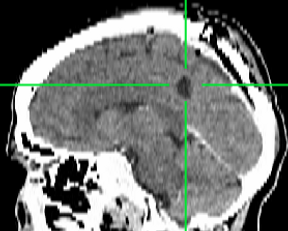

Spotāns intracerebrāls saasiņojums (hematoma)

Redzams saasiņojums smadzeņu vielā pirms operācijas

Pēcoperācijas attēls - saasiņojums no smadzenēm evakuēts